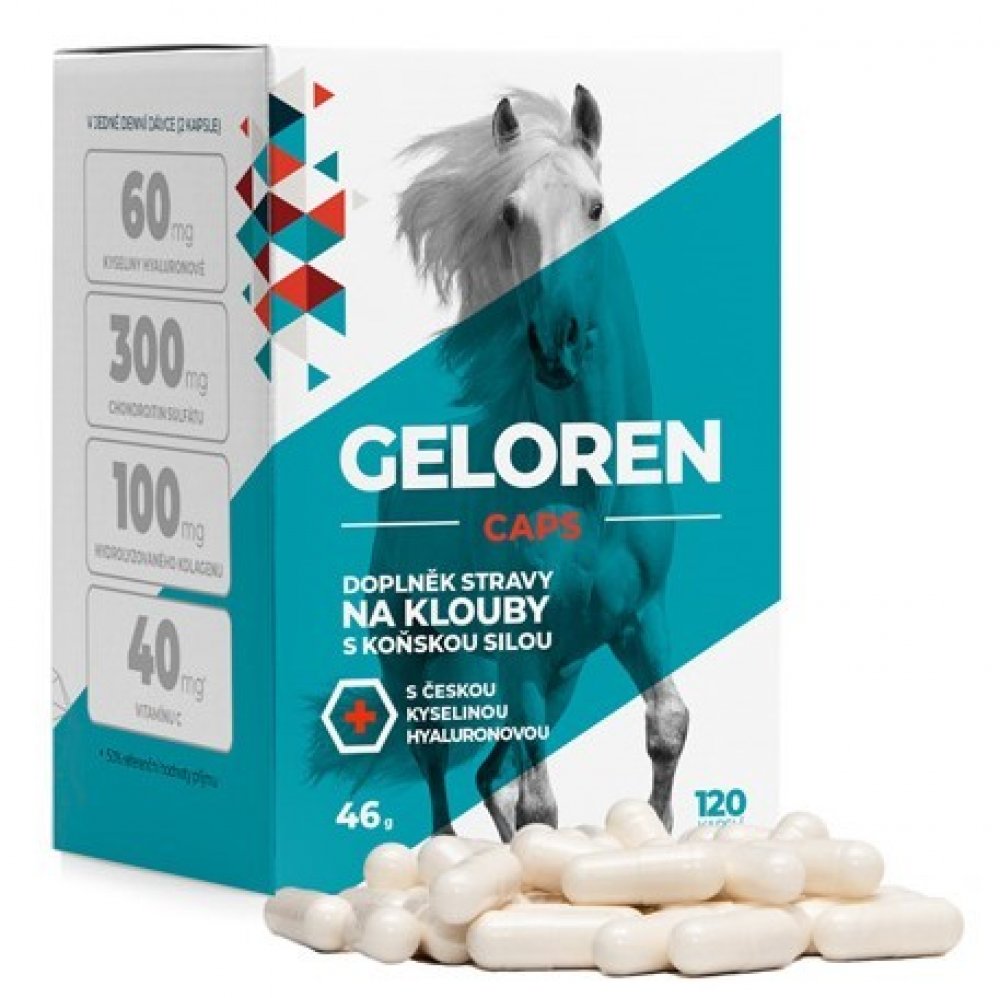

Geloren Caps 120 kapslí

Contipro a.s. 120 tbl kapsle klouby, kosti, svaly unisex 46.0 g Geloren pro dospělé perorální bez příchutě Česká republika kolagen kosti a klouby s postupným uvolňováním 60 100.0 mg Kdykoliv 2 za den Pokojová teplota (do 25°C) s vitamínem C

Geloren CAPS – chytrá kloubní péče v kapslích (bez cukru)

Když se začnou ozývat klouby, většinou to není „ze dne na den“. Je to součet sportu, práce, věku, regenerace i toho, jak dlouho tělo jede bez podpory. Geloren CAPS je praktická forma kloubní výživy v kapslích – bez žvýkání, bez pachuti a hlavně bez cukru.

- Kyselina hyaluronová + chondroitin + kolagen + vitamín C

Co najdete v denní dávce (2 kapsle)

- Kyselina hyaluronová – 60 mg

- Chondroitin sulfát – 300 mg

- Hydrolyzovaný kolagen – 100 mg

- Vitamín C – 40 mg (50 % RHP) – přispívá k normální tvorbě kolagenu pro normální funkci chrupavek

Složení

Obsah kapsle: chondroitin sulfát, hydrolyzovaný kolagen, kyselina hyaluronová, protispékavá látka – stearan hořečnatý, vitamín C (kyselina L-askorbová).

Obal kapsle: bovinní želatina, oxid zinečnatý.